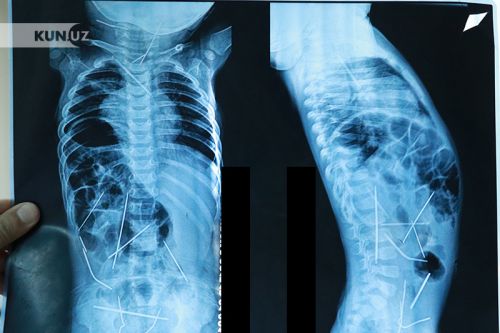

Ранее стало известно, что 11-месячного ребенка с температурой и начавшейся пневмонии из Ферганской области доставили в РНЦЭМП. При осмотре врач рекомендовал сделать рентген, во время которого выяснилось, что в теле малыша находится 16 металлических игл. Анализы показали, что они находятся там около полутора месяцев, отмечает ca-news.org

В ходе операции, которая длилась девять часов из тела малыша извлекли 13 игл, оставшиеся медики планировали удалить в ходе следующего хирургического вмешательства. Заведующий детским отделением РНЦЭМП профессор Хабибулла Акимов уверен, что ребенок не мог сам проглотить 16 иголок, так как рентген показал, что иглы находились в разных местах тела. По его словам, "иглы были вставлены посторонним человеком".